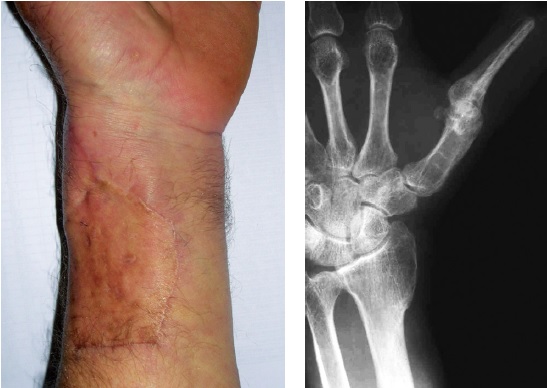

Восстановление чувствительности рабочей поверхности вновь сформированного I пальца кисти при использовании островкового кожно-костного лучевого лоскута, выделенного на дистальной сосудистой ножке, обеспечивали путем одномоментного или отсроченного перемещения дополнительного островкового ладонного пальцевого лоскута с III или IV пальца кисти. Только в 8 (29,6%) наблюдениях, помимо островкового кожно-костного лоскута, был использован ладонный пальцевой лоскут с III или IV пальца для замещения ладонной поверхности нового пальца, в остальных 19 (70,4%) случаях никакой дополнительный лоскут не применялся. Клинический пример успешной реконструкции I пальца кисти островковым кожно-костным лучевым лоскутом представлен на рисунке 1.

Рис. 1. Клинический пример успешной кожно-костной реконструкции I пальца лучевым кожно-костным лоскутом: a — вид до операции; b — рентгенограмма до операции; c — выделен кожно-костный лучевой лоскут и ладонный-пальцевой лоскут с IV пальца; d — рентгенограмма после операции; e — рентгенограммы через год после операции; f — вид кисти и функция через год после операции

Fig. 1. The clinical example of the osteo-cutaneous reconstruction of the thumb finger: a — the hand before surgery; b — X-ray of the hand before surgery, thumb lost at the proximal phalanx base; c — prepared osteo-cutaneous flap on the radial vascular; bundle and the palmar island flap from the IV finger; d — X-ray of the hand after surgery; e — X-ray of the reconstructed thumb a year after the surgery; f — appearance and function of the hand one year after surgery

В донорской зоне ни в одном случае не выявлено грубых рубцов или деформации (рис. 4).

Рис. 4. Внешний вид и рентгенограмма донорской зоны через год после реконструкции

Fig. 4. View and X-ray of the donor area one year after reconstruction